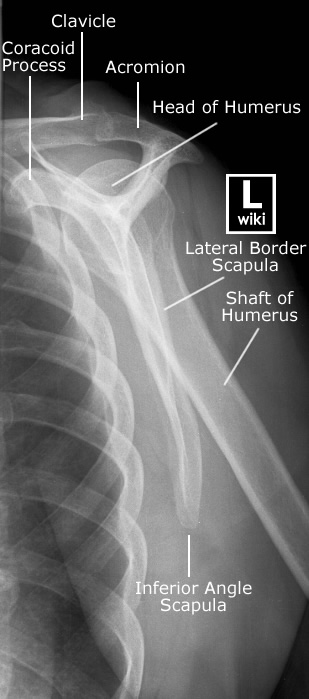

| [Anatomy] Shoulder(어깨) (0) | 2024.01.24 |